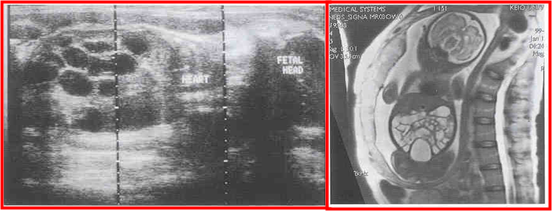

多个肠扩张 蜂巢状分布

胎儿MRI

空肠高位闭锁--三泡征

小肠低位闭锁--多数液平面